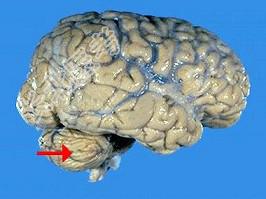

- 单项选择题如图箭头所示为颅脑哪个部位 ( )

A、顶叶

B、枕叶

C、小脑

D、脑干

E、额叶